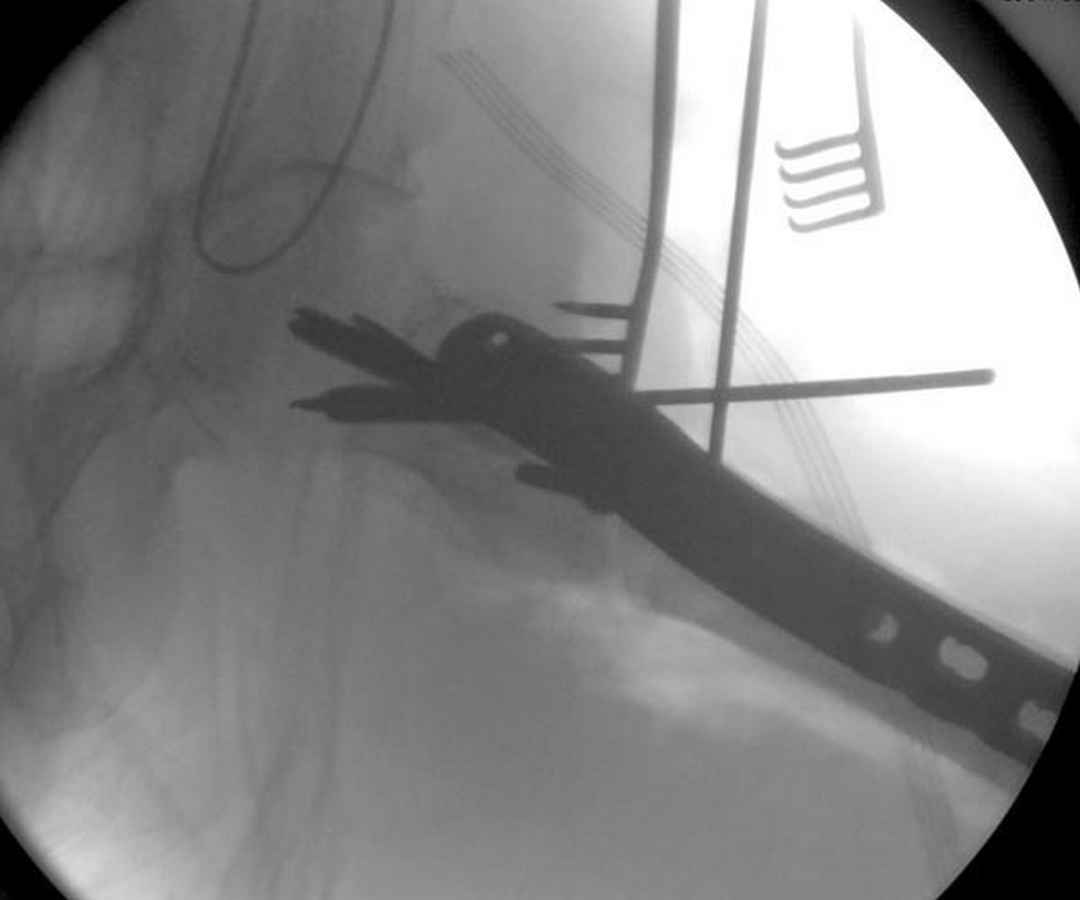

судя по картинкам с ЭОПа явно использовались приемы непрямой репозиции под его контролем, а так же интраоперационный ЭОП-контроль положения винтов, без такого контроля операция может ухудшить ситуацию (опять же учтите сроки) т.к. результат буде зависеть в большей степени от искусства хирурга, а не от технологии

Здесь пара случаев фиксации похожих переломов:

первый высокоэнергетическая травма 36 лет